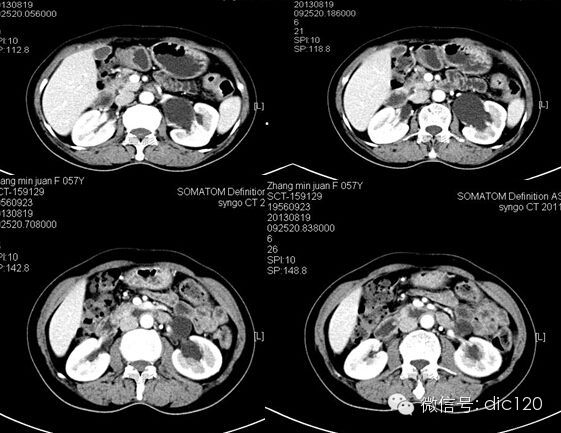

F,56Y,左腰腹部疼痛3天,B超:左肾积水,左输尿管上段扩张。

结果:卵巢静脉综合征,患者有外压性输尿管梗阻,卵巢静脉与输尿管交叉处有粘连。